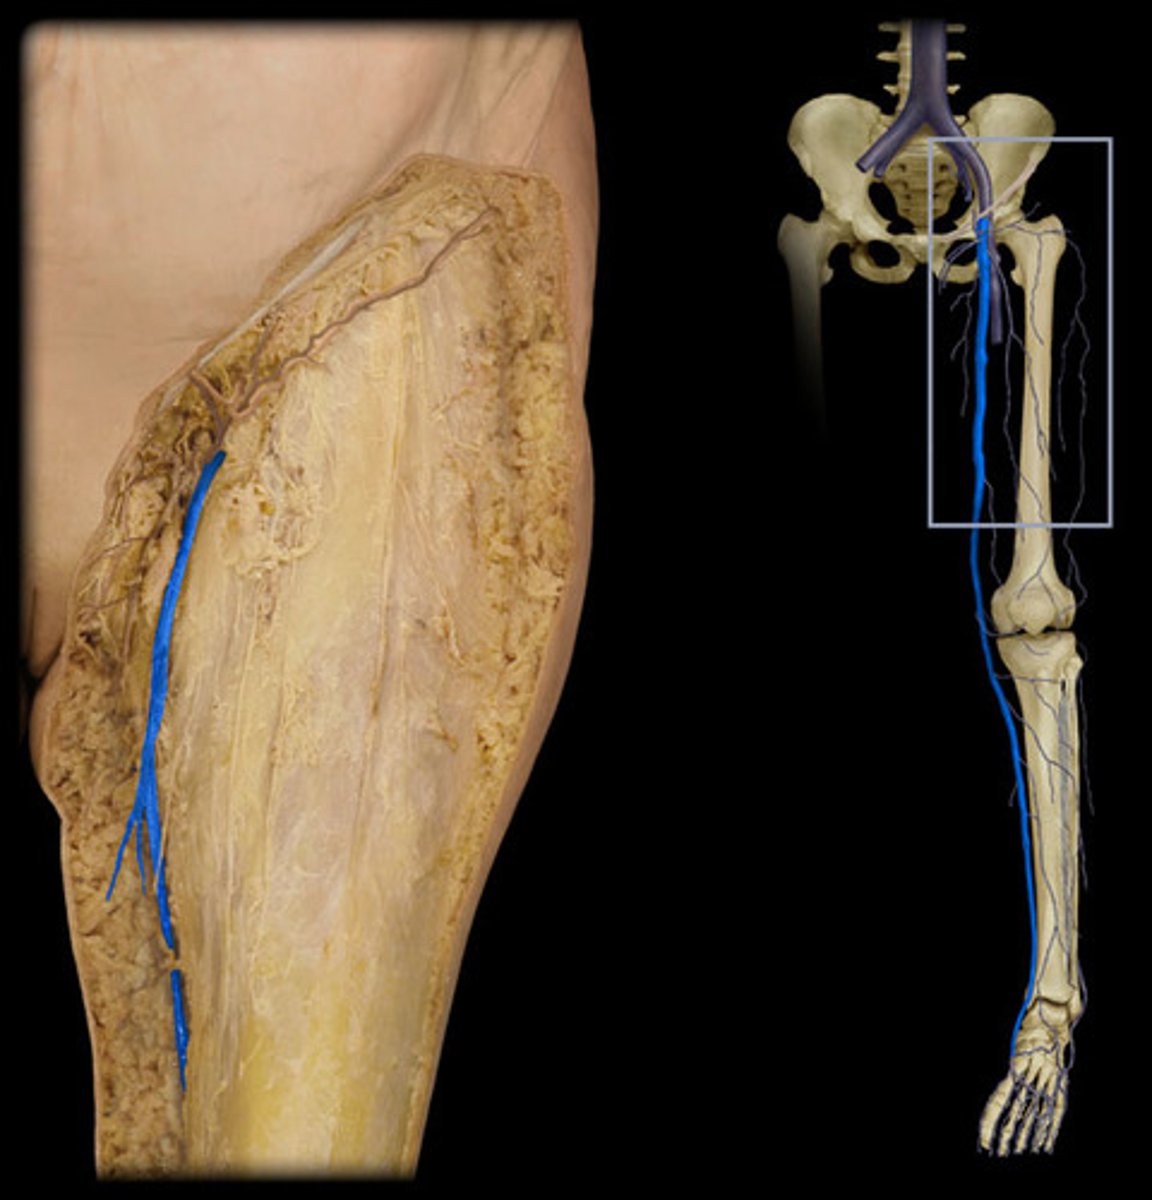

great saphenous vein

Which vein is the longest vein in the body?